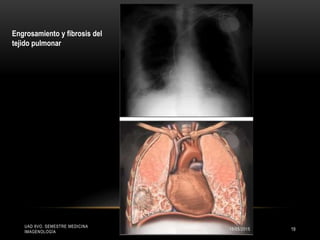

Engrosamiento y fibrosis del

tejido pulmonar

ANATOMIA PATOLOGICA

La patología consiste en neumoconiosis por

asbesto con:

Derrame pleural

Engrosamiento de las cisuras pulmonares

interlobares

 Borramiento de los senos costodiafragmáticos

y cardiofrénicos

Engrosamiento de las pleuras

Infecciones pulmonares por gérmenes

oportunistas,

Hipertensión venocapilar y arterial pulmonar.